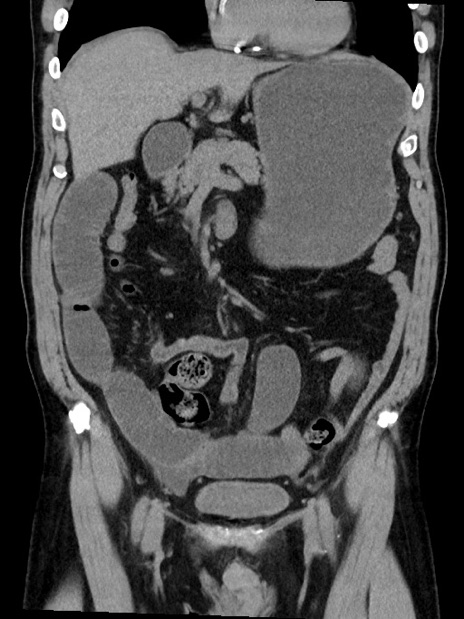

症例35(冠状断像)

【症例】70歳代 男性

【主訴】腹部膨満、嘔吐

【現病歴】昨日より腹部膨満感出現。本日増悪し、仙痛出現。嘔吐あり、受診。

【既往歴】糖尿病、胆摘後

【身体所見】BP 149/80mmHg、HR 74/min、BT 35.9℃、腹部:膨満、軟、圧痛なし。腸雑音減弱あり。上腹部正中切開瘢痕あり。

【データ】WBC 13500、CRP 1.72